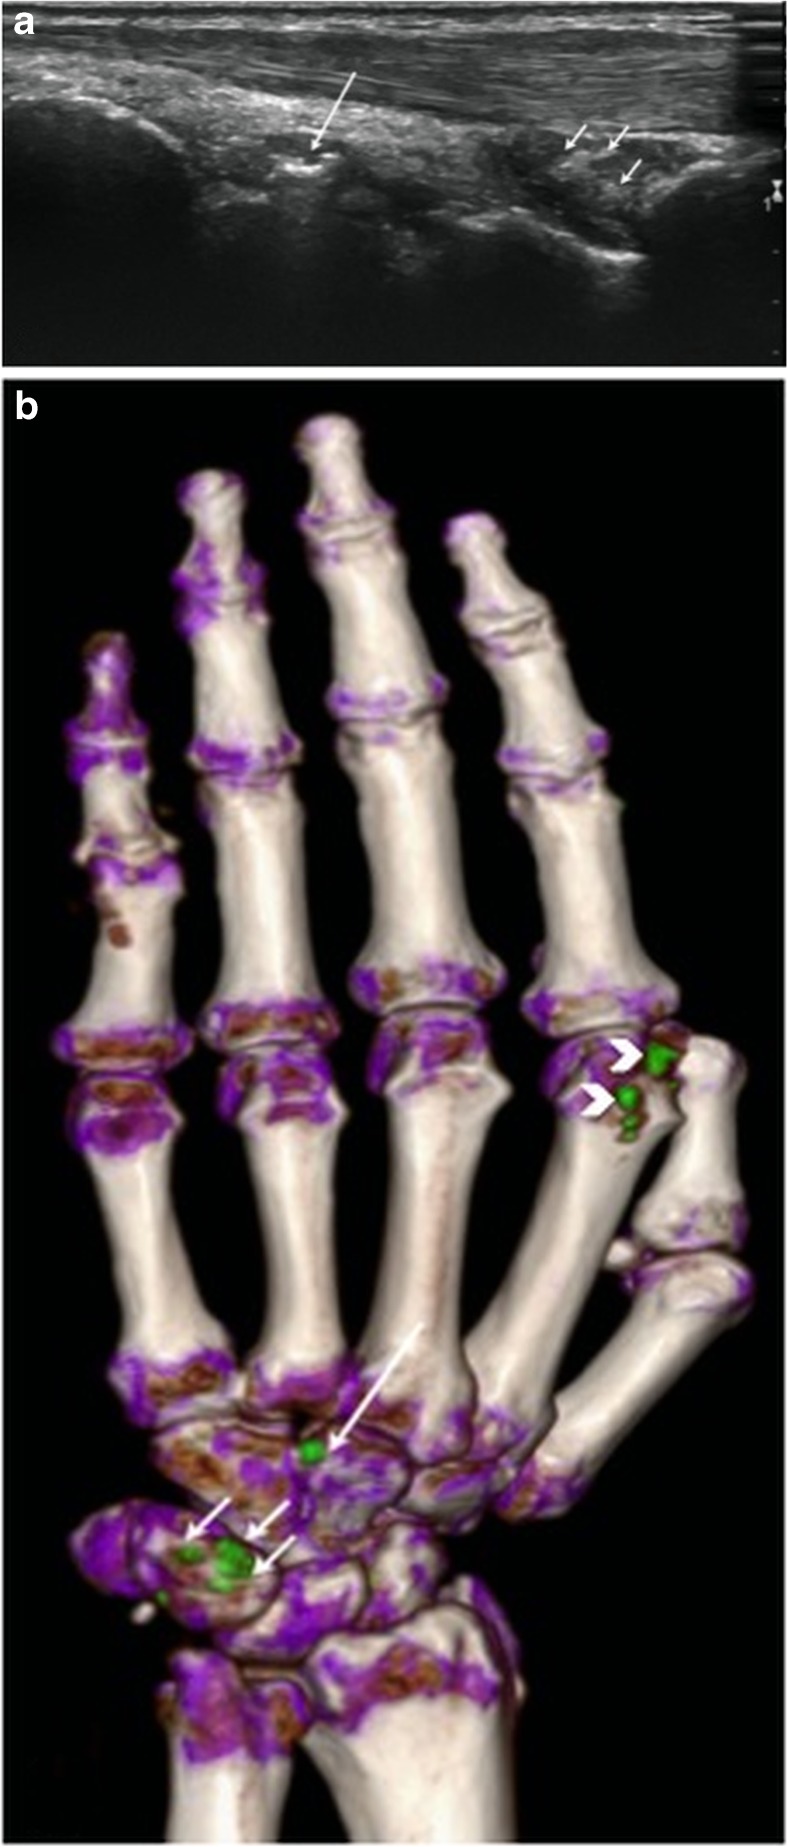

Fig. 1.

Right hand of a 77-year-old male patient. Longitudinal ultrasound (US) scan of metacarpophalangeal (MCP) joint showing double contour sign (arrows). Neither tophi nor aggregates can be seen. Dual-energy CT (DECT) of the same joint (not shown) was negative

Fig. 2.

Left hand of a 56-year-old female patient. a Longitudinal US scan over the dorsal wrist shows small echogenic deposits in the radiocarpal joint (short arrows) and intercarpal joint (large arrow), but no typical aggregates or tophi and was rated as indeterminate case. b DECT 3D volume rendered image of the same hand showing MSU deposits at the radiocarpal joint (short arrows) and intercarpal joint (large arrow). Note: MSU deposits at dorsal aspect of 2nd MCP joint (small white arrow heads)